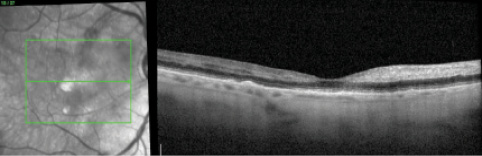

Fluorescein angiography (FA) OD revealed a marked delayed transit time of 40 seconds, poor arterial and venous perfusion, early blocked fluorescence, and hyperfluorescence without late leakage (Figures 3 and 4). SD-OCT imaging revealed drusen without intraretinal or subretinal fluid and nasal hyperreflectivity of the inner retinal layers consistent with acute ischemia (Figure 5). The patient was diagnosed with combined CRAO and CRVO.

Figure 5. OCT OD shows nasal hyperreflectivity of the inner retinal layers consistent with acute ischemia.